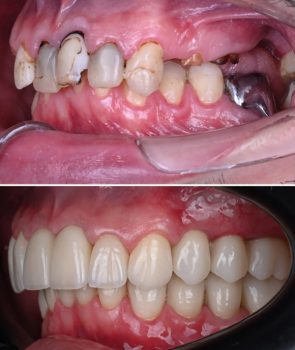

A Cone Beam Computed Tomography (CBCT) Scan is a high-tech 3D imaging system nga mas precise kaysa traditional X-rays. Makita sa dentist ang detailed structure sa imong bones, teeth, nerves, and soft tissues—perfect for:

Dental implants (exact bone measurement)

Wisdom tooth extraction (avoid nerve damage)